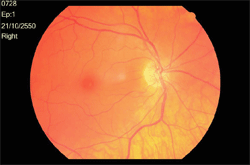

ภาพแสดงจอประสาทตาปรกติตาขวา

ภาพแสดงจอประสาทตาปรกติตาขวา สังเกตได้ว่าพื้นผิวมีสีส้มสว่างกว่าภาพแรก ซึ่งเกิดจากการที่มีเม็ดสี ( pigment ) น้อยในคนผิวขาว เมื่อเปรียบเทียบกับคนผิวเหลืองหรือผิวดำ